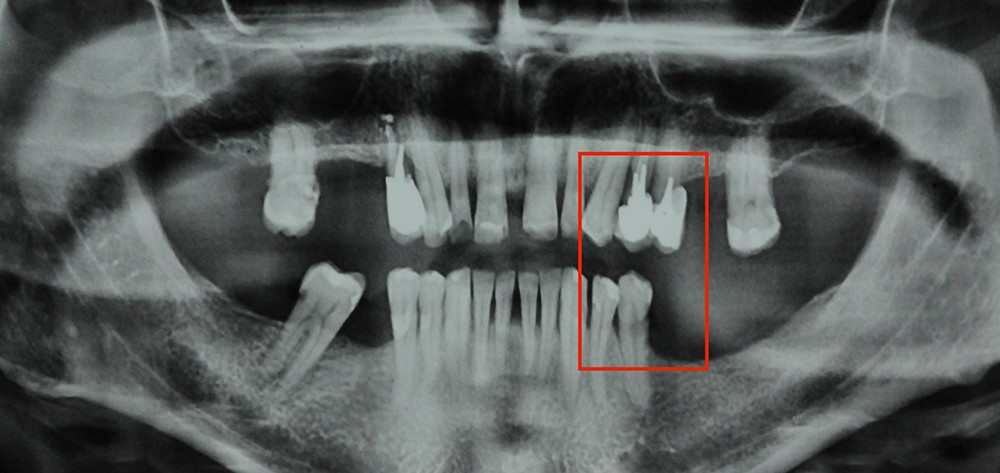

Aspect clinique et radiographique des lésions d’abrasion

Cliniquement, les lésions d’abrasion sont caractérisées par des facettes lisses, une absence de convexité et des bords à angles vifs. La flexibilité du ligament alvéolo-dentaire va entrainer un frottement au niveau des points de contact, qui peuvent se transformer en surfaces de contact (fig. 2c-d, 3 et 4b-c).

Radiographiquement, on observe une perte des cuspides et un aspect plan des faces occlusales (fig. 2a-b et 4a).